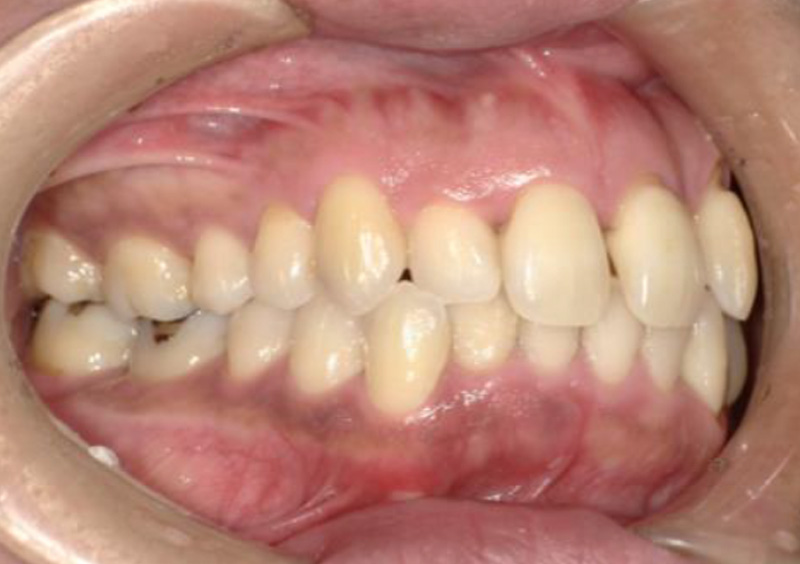

大人の矯正治療 歯ががたついている(叢生) 2025.10.22 【マルチブラケット矯正】前歯のがたつきが気になる 治療前 治療後 担当医 一瀬 悠依華 先生 主訴 前歯のがたつきが気になる 期間 1年 費用 39万円 治療内容 マルチブラケット装置(上下前歯部分矯正) 治療に伴うリスク 歯根吸収、歯肉退縮 関連症例